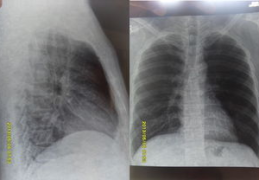

【VIP体验】我想要看胸片曝光照片怎么办,专业操作与注意事项

你有没有过这样的经历:医生让你去做个胸片检查,结果拿到照片一看,上面那些密密麻麻的线条和阴影,让你一头雾水,心里直打鼓。别担心,你不是一个人。很多人在面对胸片曝光照片时,都会感到困惑和不安。其实,只要...